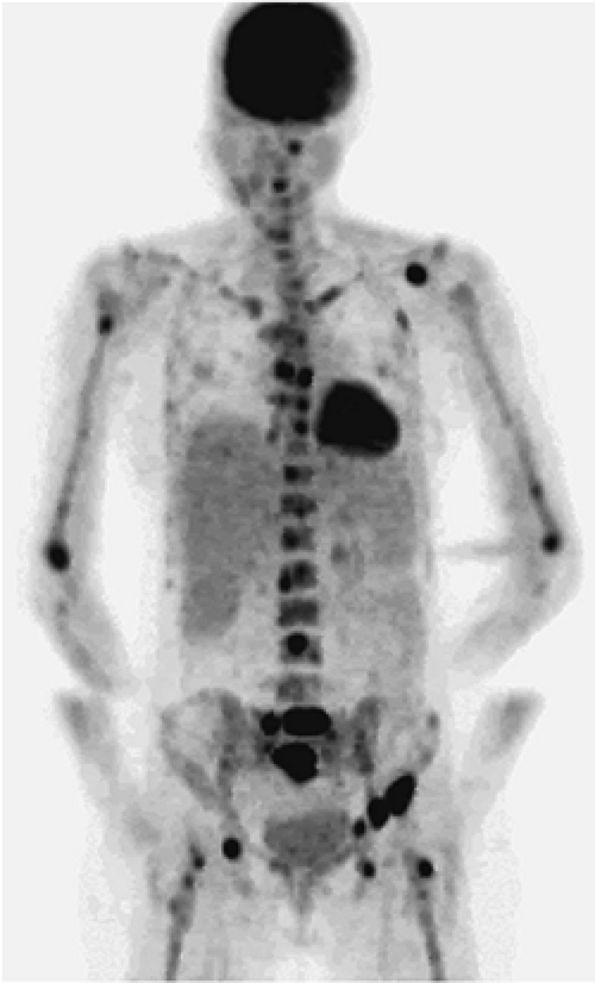

![]() |

FIGURE 13.33 ● Whole-body FDG-PET scan in a patient with lymphoblastic lymphoma. Large mass with abnormal FDG uptake is noted involving the upper mediastinum (white arrow). Increased uptake is noted throughout the spine (black arrows), the pelvis, and the proximal femurs (white arrowheads). Foci of increased uptake in the liver are consistent with tumor involvement (black arrowheads).